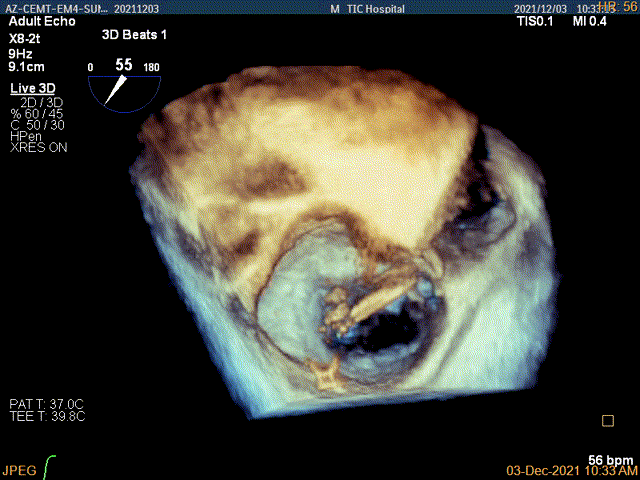

3D视图菲薄的卵圆窝,穿刺点位近似于3点位

3D视图下大鞘位置及长度测量